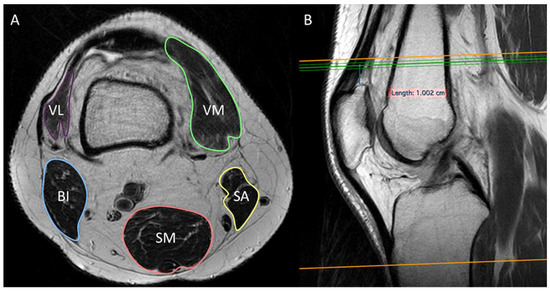

2.2. Knee MRI Protocol and Images Analysis